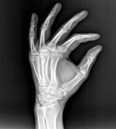

2、想象力强。医学影像学是一门以图像为基础的专业课,学习过程中主要是通过观察大量的图片培养分析问题、处理问题的能力。学生必须学会对影像图像的直观认识、三维空间思维,建立起各种影像间的立体联系,可大大增强对疾病多方面影像的认识能力。对将来阅读CT、DSA(数字减影血管造影)、MRI片和超声声像图大有裨益。